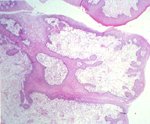

腫瘤物由數個軟組織團塊所形成,觸感硬,白色,長約 2.5 公分 × 寬約 l.5 公分,表面有出血及潰瘍現象(圖一)。 三、 組織病變: